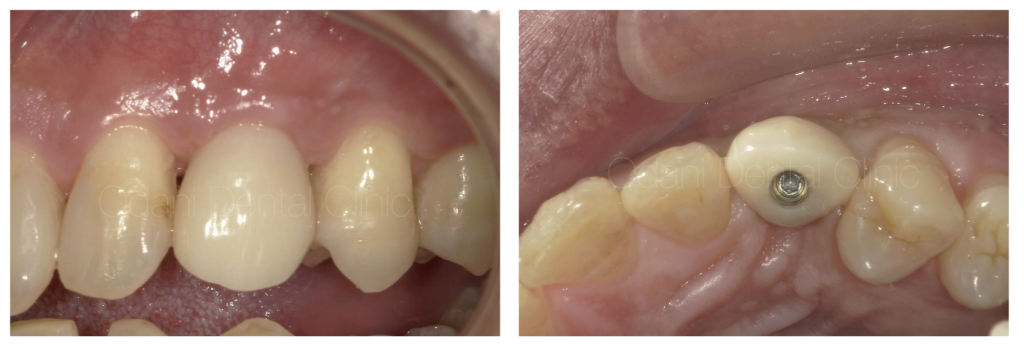

最終上部構造(ジルコニアセラミック)装着時です。歯ぐきと調和して、歯ブラシ、フロスにて清掃できる状態に仕上がりました。

治療終了後半年 歯ぐきがインプラントの歯と馴染んで安定して経過しています。